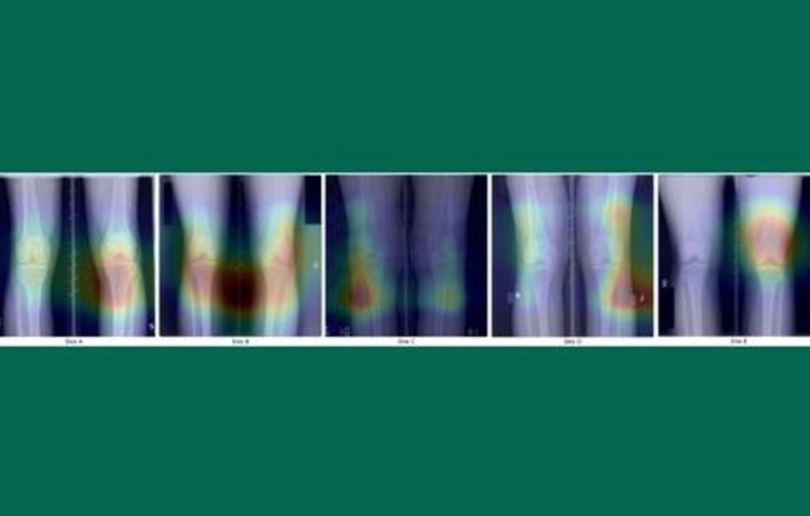

A szakemberek 25 ezer térdröntgen-felvétel átvizsgálásával bizonyították, hogy az MI-modellek képesek „megjósolni” nem összefüggő és valószínűtlen jellemzőket. A mélytanulási algoritmusok egyik legnépszerűbb típusát, konvolúciós neurális hálózatokat (CNN-eket) képeztek ki egy bizarr feladatot végrehajtására: pusztán a térdröntgen-felvétele alapján jósolják meg, hogy a páciens eszik-e a sült babot vagy iszik-e sört. A modell ezt meg is tette: 63 százalékos pontosságot ért el a bab és 73 százalékos pontosságot a sör esetében.

Mindez meglepő, hiszen nincs kapcsolat a térd anatómiája és az étrendi preferenciák között, a modellek statisztikailag mégis szignifikáns eredményekre jutottak, mutatva, hogy képesek kihasználni az adatok nem összefüggő mintáit. Ezzel a „shortcut learningnek” (lerövidített tanulásnak) nevezett jelenség iskolapéldáját adták. A shortcut learning során az MI-modell megtanul egy feladatot megoldani az adatokban jelenlévő hamis összefüggések alapján, eltérően a feladattal közvetlenül összefüggő jellemzőktől. Ilyen tanulás akkor következik be, amikor az MI-modellek az adatok felületes mintáit használják ki, ahelyett, hogy értelmes kapcsolatokat tanulnának. Az orvosi képalkotásban ez azt jelenti, hogy a modell nem ismeri fel az egészségügyi állapotokat, hanem irreleváns nyomokhoz ragaszkodik.

„Ezek a modellek olyan mintákat látnak, amelyeket az emberek nem képesek, de nem minden általuk azonosított minta értelmes vagy megbízható. Kulcsfontosságú, hogy felismerjük ezeket a kockázatokat a félrevezető következtetések elkerülése és a tudományos integritás biztosítása érdekében” – figyelmeztet Peter L. Schilling, ortopéd sebész, a tanulmány vezető szerzője. Brandon G. Hill társszerző pedig azt húzza alá, hogy az algoritmus képes megjósolni akár a röntgenfelvétel évét is, ami káros. Ha viszont a programozó megakadályozza, hogy megtanulja az egyik elemet, akkor ehelyett megtanul egy másikat, amelyet korábban figyelmen kívül hagyott. Ez a veszély nagyon fura állításokhoz vezethet, és a kutatóknak tisztában kell lenniük azzal, hogy ez milyen könnyen megtörténik, ha ezt a technikát használják. Az irreleváns, de statisztikailag szignifikáns összefüggések feltárásával történő „csalás” képessége komoly kockázatot jelent az orvosi alkalmazások számára.

A Dartmouth Health kutatói úgy gondolják, hogy a shortcut learning kockázata különösen aggodalomra ad okot az orvosi képalkotásban (pl. röntgen-, CT-vizsgálatok stb.), ahol a gépi tanulástól remélik a diagnózis, és így a kezelés minőségének és hatékonyságának javítását. Éppen ezért sokkal komolyabb ellenőrzésnek kell alávetni az MI-t, különösen orvosi környezetben.